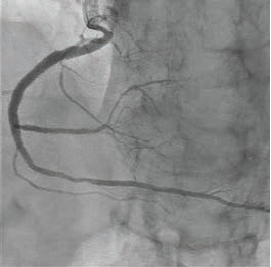

We use IVL in lesions with evidence of severe calcification, either angiographically or by using other forms of imaging like intravascular ultrasound (IVUS) or optical coherence tomography (OCT). Often these complex lesions lead to issues with stent delivery and optimization. IVL has been shown to be a safe and efficient way to modify calcium before stenting. Other forms of traditional calcium modification such as orbital or rotational atherectomy have an elevated risk profile and many people are hesitant to use them because of the risk involved, especially if surgical backup is not available. Having a safe mechanism available like IVL allows us to more effectively treat patients with severely calcified lesions.

Because of the limitations of the prior catheter, we developed several strategies for pulse conservation with IVL. One option is using intravascular image guidance as a way to target areas of severe calcification for treatment. For example, OCT has built-in algorithms to determine the depth and degree of the arcs of coronary calcium. We can employ these algorithms to help focus therapy on those diseased areas. Similarly, we can use IVUS to identify areas where there is concentric or nodular calcium that would potentially need modification, and spare therapy in less diseased sections of the artery.

Sometimes identifying areas for treatment is as simple as inflating the IVL balloon. At 4 atmospheres, if you are able to get full expansion of the balloon, then that area may not benefit as much as areas without expansion. Subsequently, after IVL treatment, I dilate with a 1:1 noncompliant (NC) balloon that is the size of my stent to ensure I have full expansion. If not, I focus more pulses in that area to ensure full stent expansion.